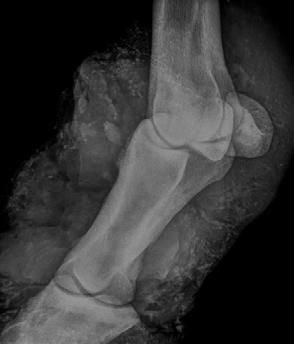

Histopathology of the pancreas confirmed necrotising pancreatitis with surrounding peritonitis and fat necrosis (Figure 3)

Additionally, pulmonary thromboembolism was identified in the lungs (Figure 4) which likely accounted for the patient’s acute respiratory distress.

Figure 3. Severe necrotising pancreatitis Figure 4. A massive pulmonary thrombusPulmonary thromboembolism (PTE) is a known but relatively uncommon complication of pancreatitis in both human and veterinary medicine. Presenting clinical signs can include an acute onset of dyspnoea/ respiratory distress and hypoxaemia. In this case, PTE was presumably due to a combination of blood hypercoagulability and endothelial injury related to the pancreatitis. Severe necrotising pancreatitis is often related to the systemic release of pro-inflammatory mediators such as TNF-a, IL-1 and IL-8 resulting in hypercytokinaemia/cytokine storms which altogether contribute to blood hypercoagulability (thrombophilia). Additionally, widespread tissue damage and necrosis inflict endothelial damage further exacerbating the patient’s thrombotic state.